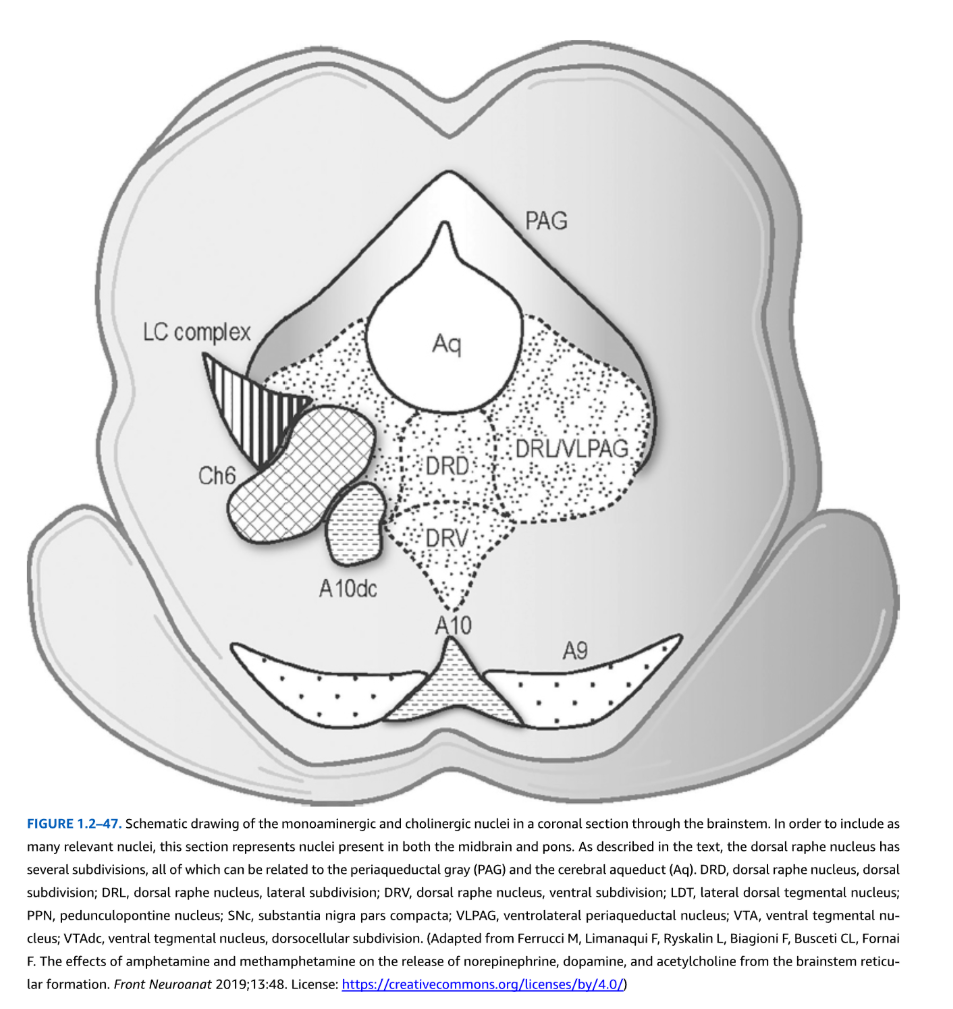

図1.2-47. 脳幹の冠状断面におけるモノアミン作動性およびコリン作動性核の模式図

関連する核をできるだけ多く含めるため、この断面は中脳と橋の両方に存在する核を表している。本文で述べられているように、背側縫線核はいくつかの下位区分を有し、そのすべてが中脳水道周囲灰白質(PAG)と大脳水道(Aq)に関連している。

略語説明:

- DRD:背側縫線核、背側下位区分

- DRL:背側縫線核、外側下位区分

- DRV:背側縫線核、腹側下位区分

- LDT:外側背側被蓋核

- PPN:脚橋被蓋核

- SNc:黒質緻密部

- VLPAG:腹外側中脳水道周囲核

- VTA:腹側被蓋核

- VTAdc:腹側被蓋核、背側細胞下位区分

(Ferrucci M, Limanaqui F, Ryskalin L, Biagioni F, Busceti CL, Fornai F. The effects of amphetamine and methamphetamine on the release of norepinephrine, dopamine, and acetylcholine from the brainstem reticular formation. Front Neuroanat 2019;13:48より改変。ライセンス:https://creativecommons.org/licenses/by/4.0/)

吻側レベルでは、背側縫線は正中線上に位置し、中脳水道周囲灰白質の腹側にあり、外側は動眼神経核と内側縦束によって境界され、尾側では中脳水道周囲灰白質の腹側に留まり、滑車神経核と内側縦束が外側境界となる。背側縫線は人間の脳で最大のセロトニン作動性ニューロン集団を含む背側縫線、外側背側縫線、腹側背側縫線を含む亜核にさらに細分される(図1.2-47参照)。